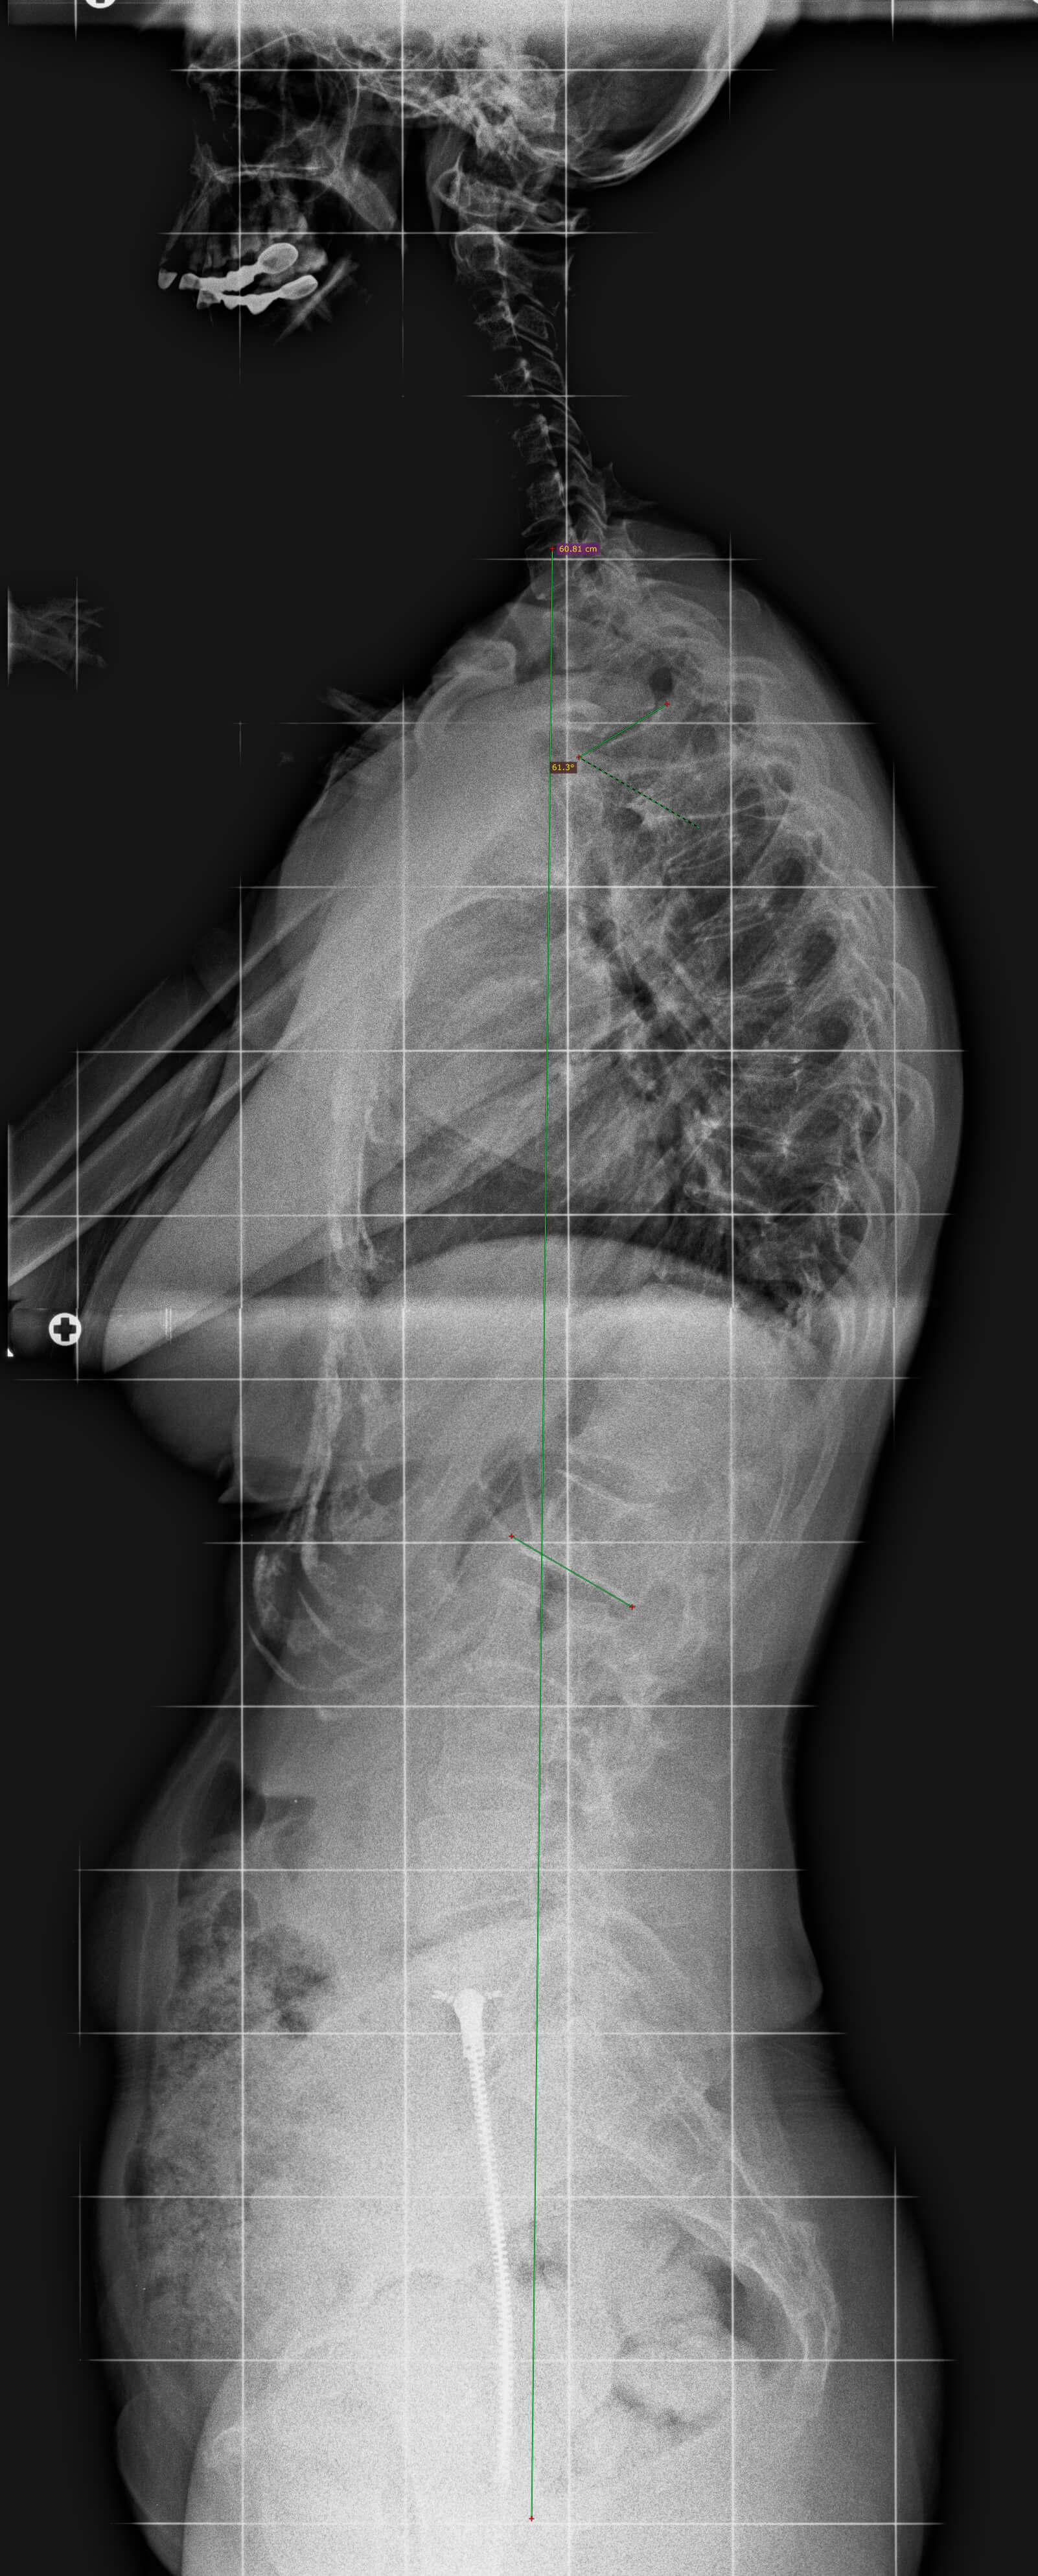

26 yaşında kadın hasta. Sırt ve bel ağrıları mevcut.

Ameliyat Öncesi